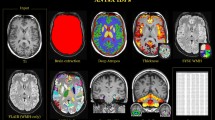

Extended Data Fig. 1 Qualitative comparison with the state-of-the-art in motion magnification.

To compare our results with Oh et al.(30), we show five clips from different impaired subjects before and after magnification for both methods. First, we re-synthesize the healthy reference behavior to change the appearance to that of the impaired subject so differences in posture can be studied directly, first row (see Method). The second row is the query impaired sequence. Third and forth rows show the magnified frame using the method by Oh et al.(30) and our approach, respectively. The magnified results, represented by magenta markers, show that Oh et al. corrupts the subject appearance, while our method emphasises the differences in posture without altering the appearance. (Details in Supplementary).